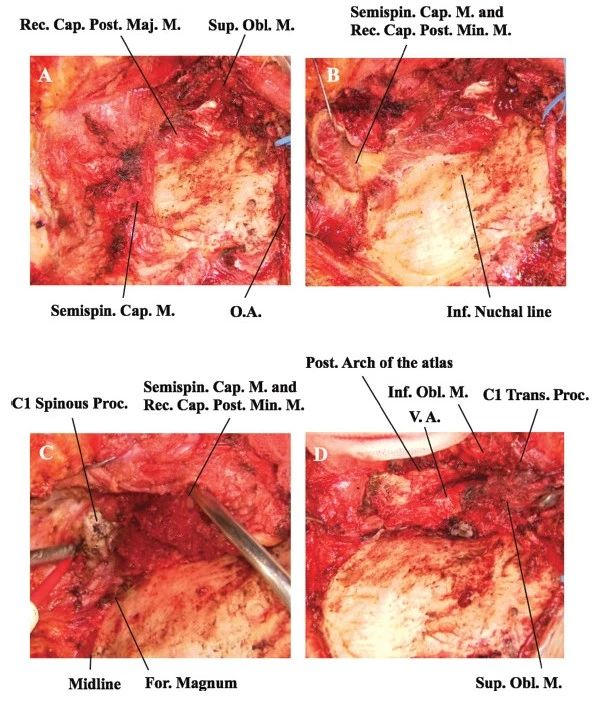

图2. 远外侧入路肌群解剖分离手术照片。A.外侧肌群分层分离显露枕下三角。B.内侧肌群自中线从骨面游离。C.枕大孔后缘和C1棘突显露。D.暴露C1后弓和椎动脉。O.A.:枕动脉;C1 Spinous Proc.:C1棘突;For. Magnum:枕大孔;Post. Arch of the atlas:寰椎后弓。

图1. 远外侧入路肌群解剖步骤示意图。A.外侧肌群从枕下三角向下翻折。B.内侧肌群从中线以单层剥离骨面,显露枕大孔后缘和C1-2棘突。C.向内/外侧分离肌群显露下斜肌和寰椎后弓。D.重要的解剖学标志。Semispin. Cap. M.:头半棘肌;Long. Cap. M.:头最长肌;Sup. Obl. M.:上斜肌;Inf. NuchalL:颈项下沟;Splen. Cap. M.:头夹肌;Stemocleidomas. M.:胸锁乳突肌;Rec. Obl. M.:头后小直肌;Rec. Cap. Post. Maj. M.:头后大直肌;V.A.:椎动脉;Occip. Cond.:枕髁;C1 Trans. Proc.:C1横突;Cond. Emissary Vein:髁后导静脉;Inf. obl. M.:下斜肌;Post. Arch of C1:C1后弓。